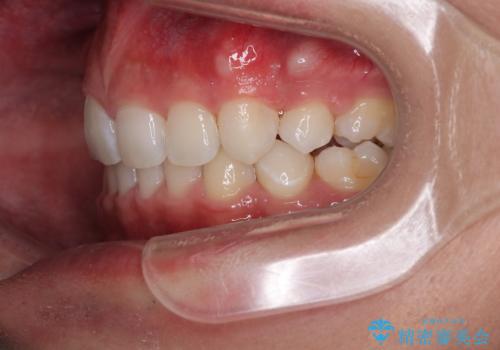

- 今回ご紹介するのは、

「全体的なデコボコ(叢生)」「上下の正中のずれ」 を主訴として来院された20代男性の患者様の症例です。

叢生が強く、歯が並ぶスペースが不足していたため、

上下左右の第一小臼歯を抜歯して、矯正治療のための適切なスペースを確保する計画としました。